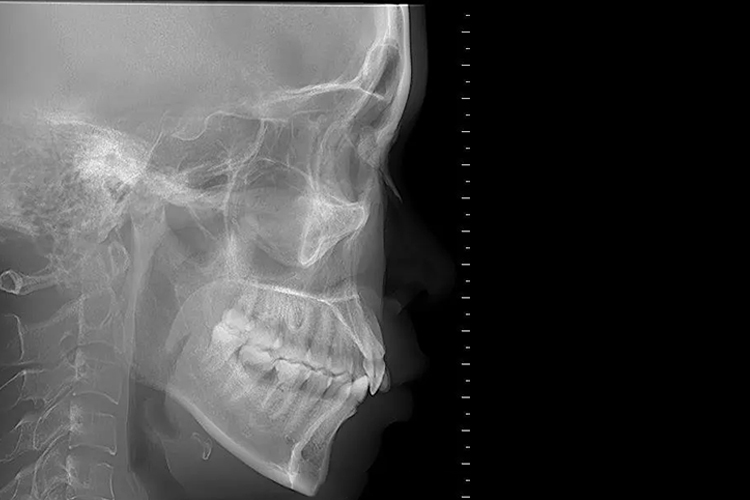

颞颌关节X线检查时需摄取两侧的侧位闭、张口位片,可显示出骨组织及含气空腔,常用于观察外伤骨折、颌面骨炎症、肿瘤性病变以及颞颌关节病变等,正常X线表现如下:

颞颌关节闭口位:X线检查可见受检者的上下颌为闭合状态,下颌骨髁状突应位于关节窝内,关节间隙约2mm,两侧颞颌关节活动度相等。